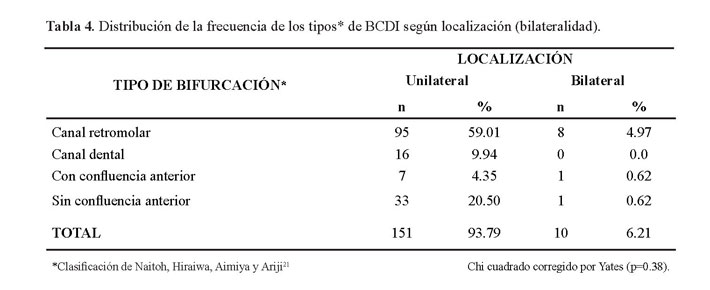

Del total de casos encontrados con BCDI el 93.79% (151 casos) fueron unilaterales y 6.21% (10 casos) bilaterales (Tabla 4).

En la tabla 5 se muestra que no hubo diferencia estadísticamente significativa entre ambos lados (p=0.78) (Figura 5 y figura 6).